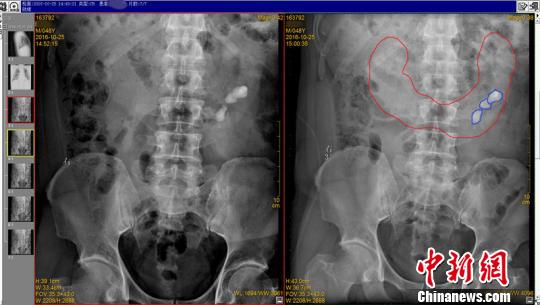

“打孔取石”4颗结石被取出

10月25日,王强又一次因为结石住进四川结石病医院,这一次,他的结石长到了4颗。因做过一次开放式取石手术,形成了瘢痕,不适宜再次手术。而更先进的纤维肾镜碎石取石,在马蹄肾复杂的内部结构中顺利找到碎石并取出的难度也较大。